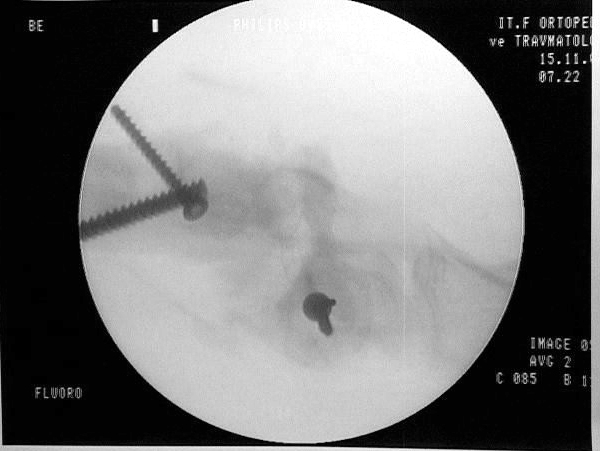

Vaka 2